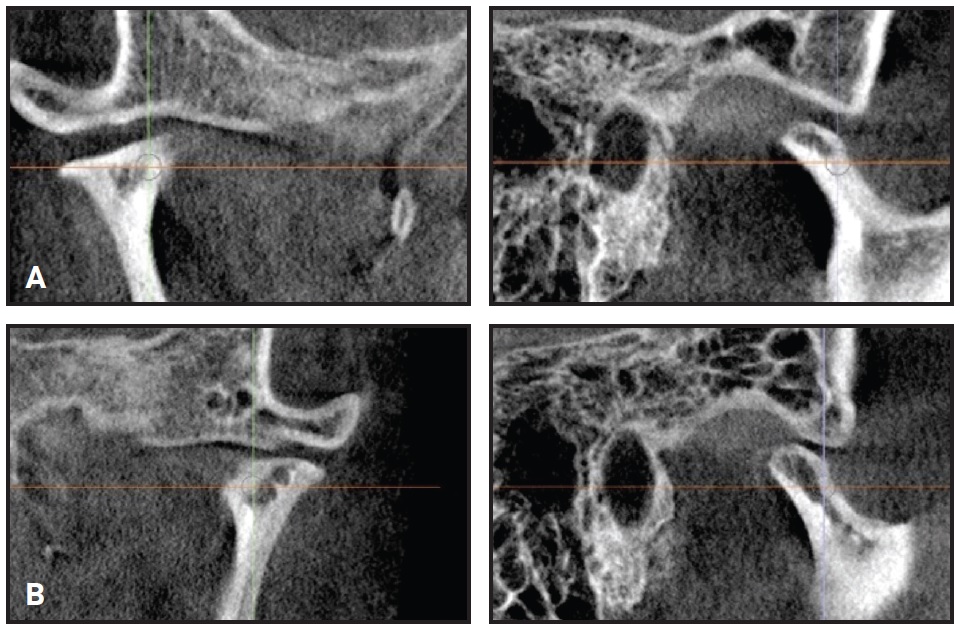

Post-treatment dental cast measurements of the WALA ridge were increased by 5mm at the mandibular canines and 2.5mm at the first premolars10 (Fig. 6).

Fig. 6 A. WALA ridge10 before treatment. B. After treatment.

This arch expansion was obtained not only by lateral tooth movement, which increased the intercanine, interpremolar, and intermolar widths, but also by alveolar bone remodeling following movement of the teeth.9

Post-treatment computed tomographic (CT) images confirmed that the integrity of the alveolar bone and the dental roots was maintained (Fig. 7).

Fig. 7 Preservation of alveolar bone tissue and dental roots after treatment.

The lower central incisors showed the greatest alveolar bone loss, but the damage was minimal. Unfortunately, a CT scan was not required before orthodontic treatment, and therefore it is not possible to determine whether this bone loss was preexistent or caused by orthodontic tooth movement. In any event, the overall results were excellent, and the cost-benefit return of the orthodontic treatment was unquestionable.